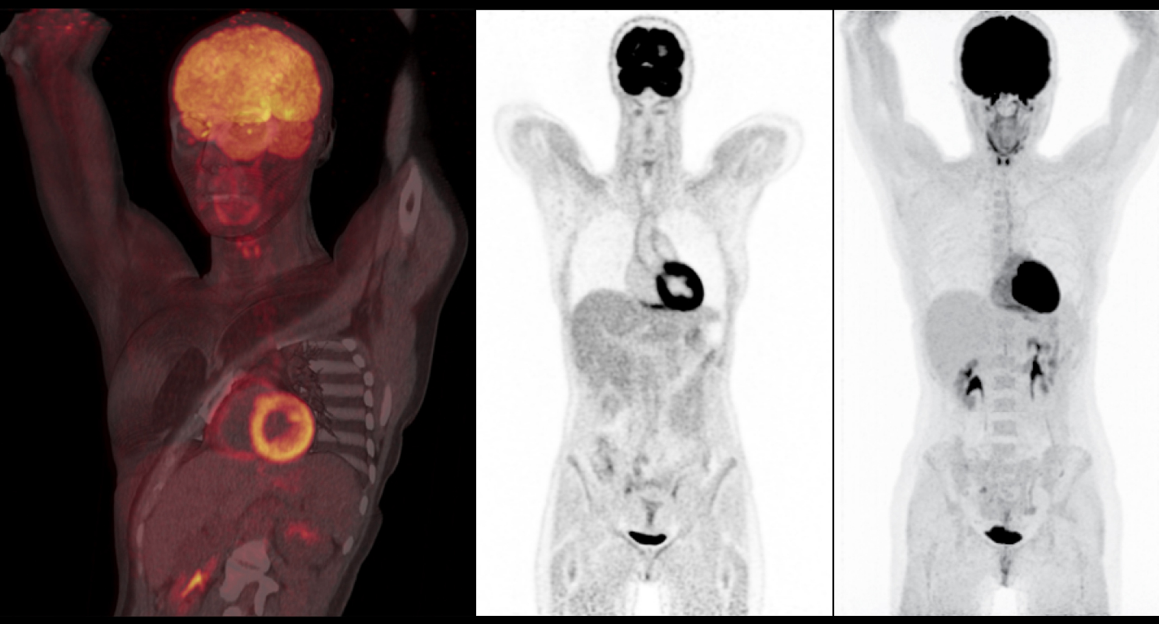

Axumin fluciclovine F 18 injection is indicated for positron emission tomography PET imaging in men with suspected prostate cancer recurrence based on elevated blood prostate.

National Pet Scan DadeLLC. Axumin fluciclovine F 18 injection is indicated for positron emission tomography PET imaging in men with suspected prostate cancer recurrence based on elevated blood prostate. If the PSA is above 2ngml the detection rate of tumor recurrence is 917.

Axumin PET CT is less sensitive for recurrent tumor detection in patients with a PSA level below 2ngml. Our dedicated diagnostic imaging scheduler can provide you with the scheduled days our Mobile PETCT coach is on site at these clinic locations. We Accept All Insurance.

The lesion was treated with SBRT and I am currently 7 months into a 2 year. The Axumin PET scan works by detecting the metabolic activity of the cancer itself. I had an Axumin PET scan earlier this year when my PSA rose to 098 and it identified a lesion in my left pubic bone.